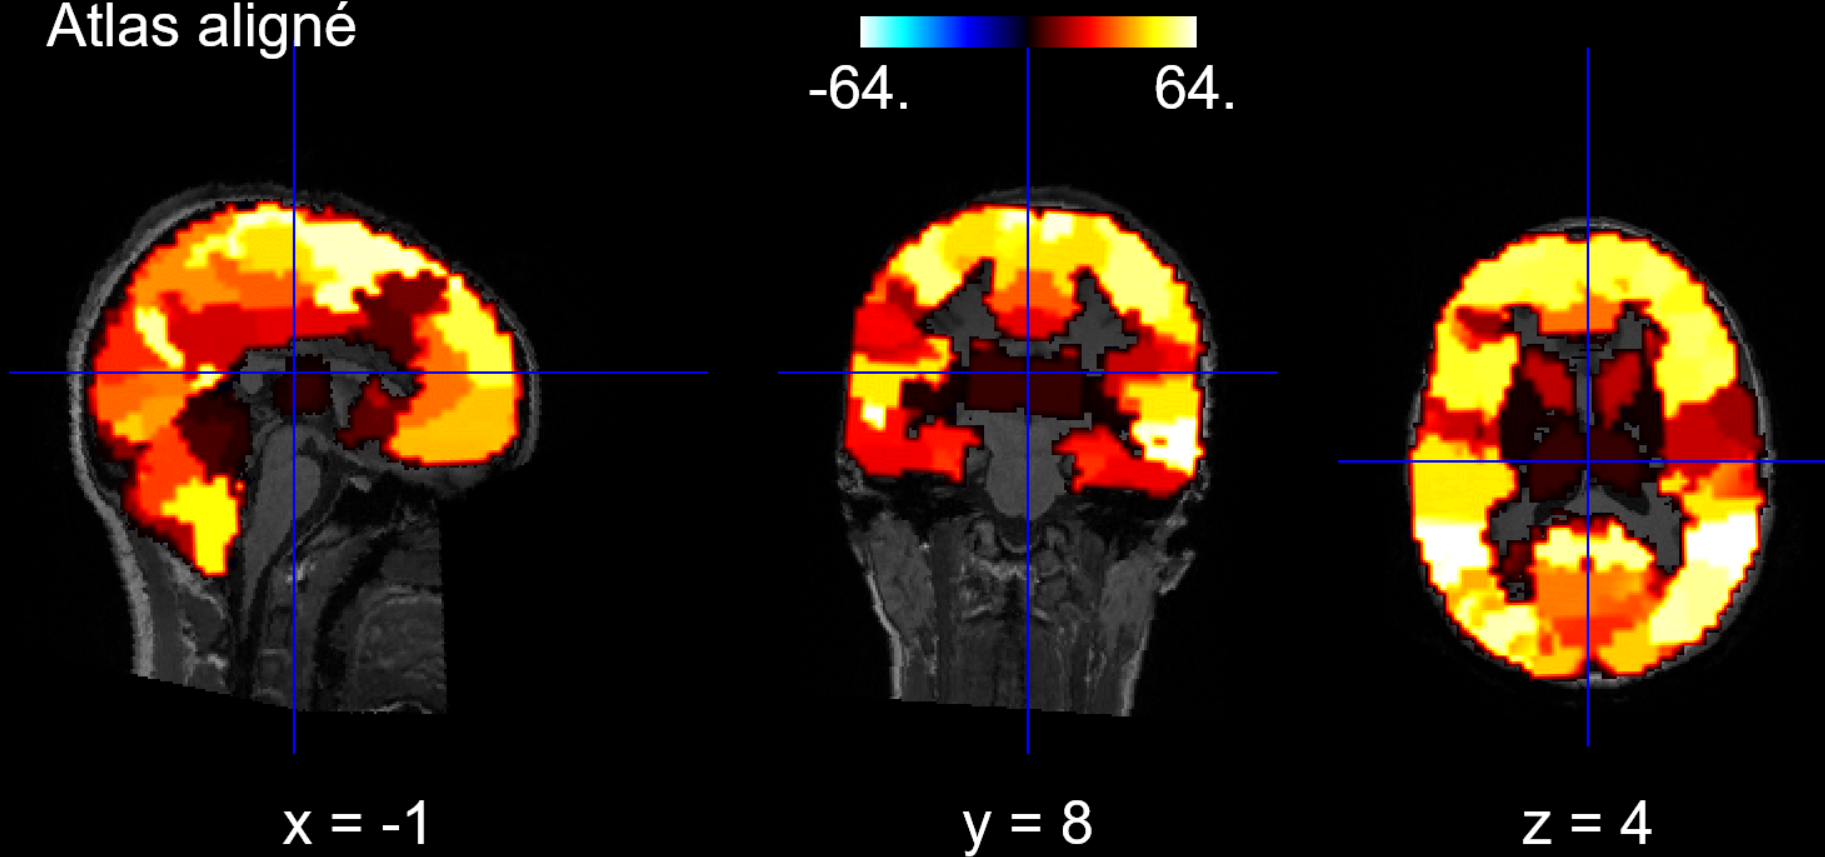

Next, we choose an atlas that allows us to define regions of interest (ROI) to focus our efforts. The chosen atlas defines 64 regions of interest:

To apply our atlas, we also need to align it to the T1 scan of each patient:

2.3 Atlas Application

Finally, since our brain is aligned with the T1 scan and the atlas is also aligned, both are aligned, and we can apply a masker to our data to define the regions of interest on our brains: